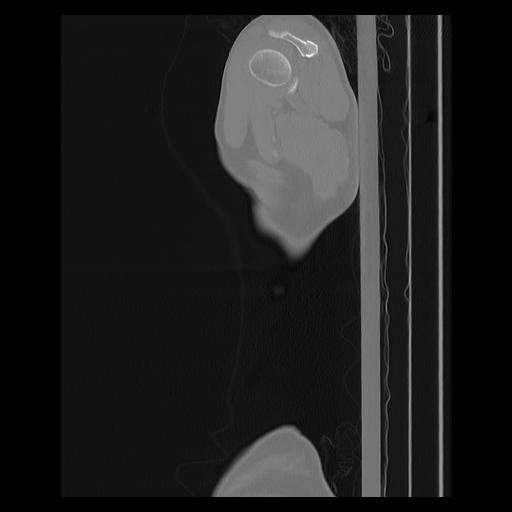

33 PULMON,CE,Sagittal,3.000,PULMON,Sagittal,